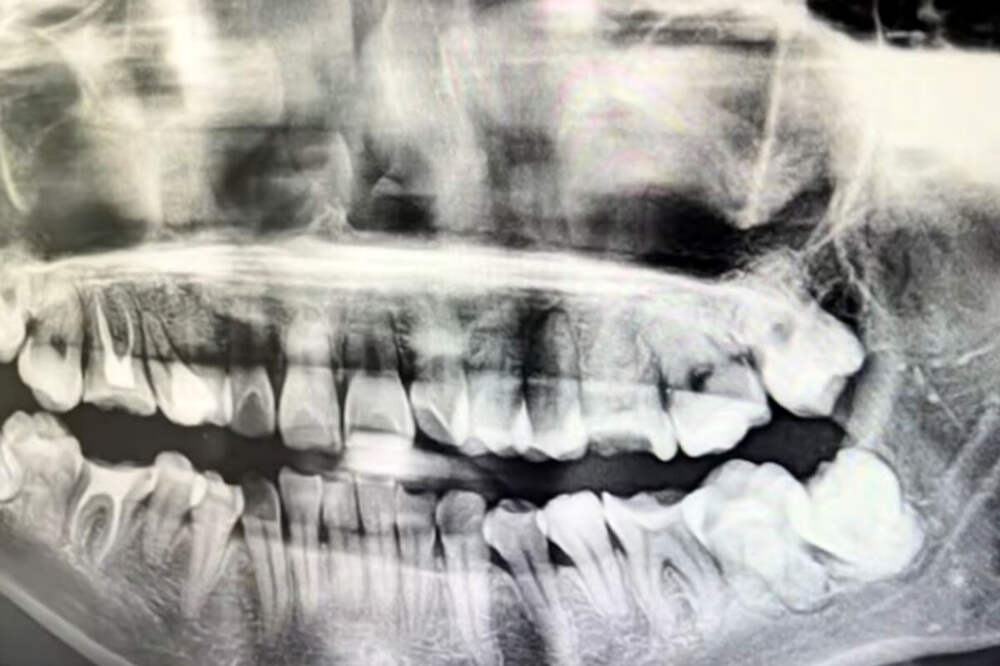

Истончение кости вокруг зубного импланта чаще всего происходит из-за естественного снижения нагрузки на костную ткань, инфекций и неправильного выбора изделия. Курение и сахарный диабет дополнительно повышают риск. Об этом "Газете.Ru" рассказал кандидат медицинских наук, врач-стоматолог–имплантолог... Далее